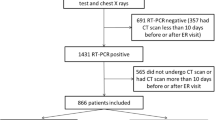

In the development cohort (from 3 university hospitals in Bordeaux, Grenoble, and Montpellier and a private hospital in Bordeaux, France), patients were eligible if they were at least 18 years old, and had a first chest CT performed without injection of contrast agent for respiratory symptoms which led to highly suspicious or compatible according to standardized visual analysis of COVID-19. Besides, they should have either a biological diagnosis (RT-PCR) or a clinical suspicion (cough and/or dyspnea and/or fever and/or need to use oxygenotherapy as part of routine care) of COVID-19 at the time of the CT scan, between March 1, 2020, and May 5, 2021 (Figure S1). Non-inclusion criteria were patients with moderate or severe forms (defined as oxygenotherapy ≥ 3 L/min to obtain a SpO2 > 97%) or critical forms of COVID-19 (defined by the need for non-invasive or invasive ventilation and/or orotracheal intubation) on the date of the first chest CT. In the validation cohort (university hospitals in Nancy and Poitiers, France), eligibility criteria were similar, except that half of the patients had chest CT with a contrast agent injection.

Validation cohort

A total of 827 participants were included in the development cohort (Fig. 1). The study demographics are presented in Table 1 and Table S3. Briefly, mean age was 65.5 [IQR 54; 79] years; there were 495 (59.9%) men, with a median BMI of 27.4 [23; 30] kg/m2 and a median time between first symptoms and CT of 6 [2; 10] days. Comorbidities were mainly hypertension (373, 45.1%), obesity (178, 21.7%), and diabetes mellitus (170, 20.6%). Asthma and COPD affected respectively 9.3 and 8.5% of the population. A positive RT-PCR during the acute phase was reported for 461 (64.8%) participants. Mean lymphocyte level was 1.16 ± 1.35 G/L, CRP 86 ± 82 mg/L. CT features were distributed as follows: ground-glass opacities affecting 805 (97.3%). The extent of the COVID-19 suspected lesions were mild (182, 22.0%), moderate (389, 47.0%), extended (200, 24.2%), severe (52, 6.3%), or critical (4, 0.5%). Finally, 440 (53.2%) participants were graded highly suspicious for COVID-19 diagnosis, the others being compatible.

Baseline characteristics and outcomes of the external validation cohort